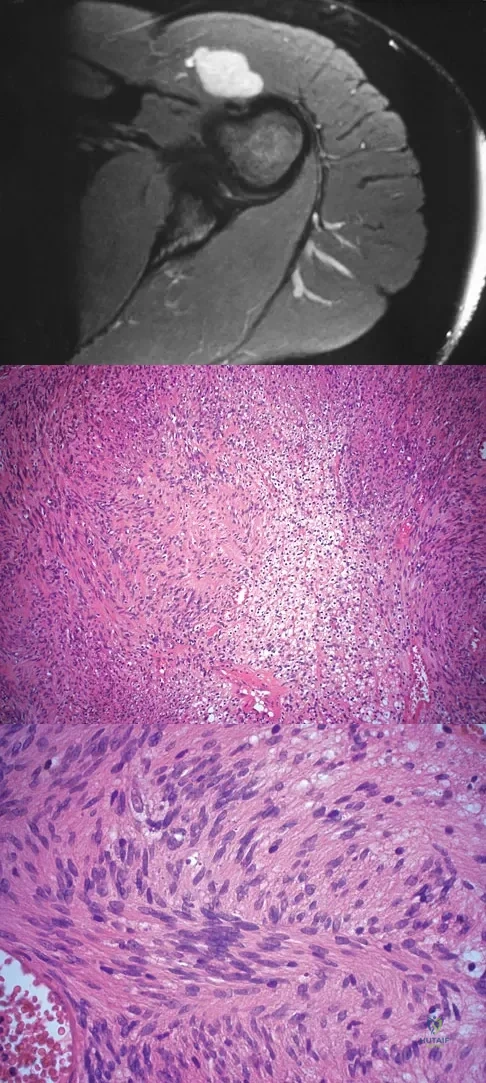

A 16-year-old girl has had hip pain for 1 year. Approximately 2 months ago she noted the development of a hard mass in the right buttock that has steadily increased in size. She now reports severe pain in the right buttock, with radiation down the leg and numbness involving the right foot and toes. A radiograph is shown in Figure 70a and an axial postcontrast T1-weighted MRI scan is shown in Figure 70b. A biopsy specimen is shown in Figure 70c. The chest CT shows multiple lung metastases. Treatment of this lesion should consist of

A 28-year-old woman has left shoulder pain and a tender soft-tissue mass. Based on the MRI scan and biopsy specimens shown in Figures 74a through 74c, what is the most likely diagnosis?